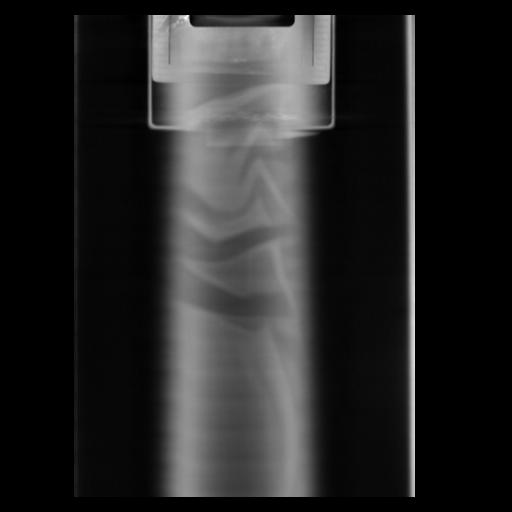

29 CUERPO,CE,Coronal,3.000,CUERPO,Coronal,